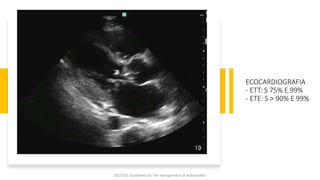

ECOCARDIOGRAFIA

- ETT: S 75% E 99%

- ETE: S > 90% E 99%

ECOCARDIOGRAFIA - ETT: S75% E 99% - ETE: S > 90% E 99% 2023 ESC Guidelines for the management of endocarditis